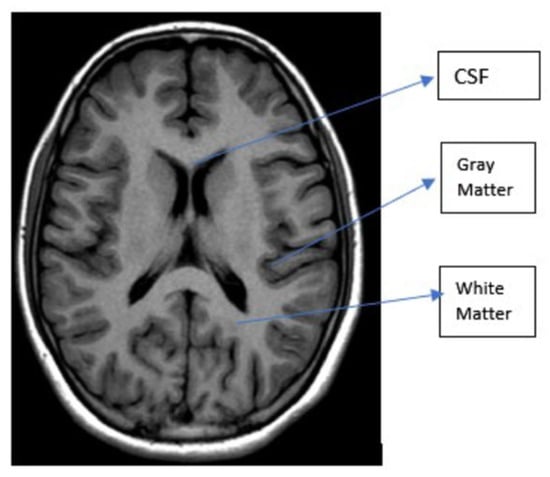

| T1 | T2 | Flair | |

|---|---|---|---|

| White Matter | Bright | Dark | Dark |

| Gray Matter | Gray | Dark | Dark |

| CSF | Dark | Bright | Dark |

| Tumor | Dark | Bright | Bright |